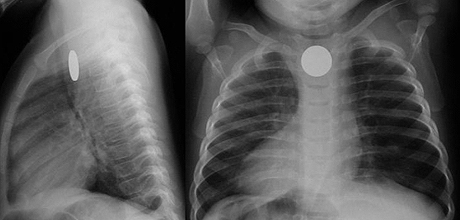

Рентген грудной клетки ребенка делали и в зеленоградской больнице, но не заподозрили на снимке наличие инородного тела. По результатам служебной проверки, «врач-рентгенолог приняла имевшуюся на снимке тень за медальон». Повторное рентгенологическое исследование дыхательных путей или пищевода не назначалось.